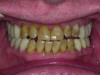

Close-up view of patient’s dentition in 2009.

Figure 1

Close-up view of patient’s dentition in 2017 showing increased facial and buccal erosion over the past 8 years.

Figure 2

Biomechanical: Significant tooth structure loss had occurred between 2009 and 2017 (Figure 1 through Figure 3). Severe attrition had occurred on the anterior teeth, especially tooth No. 11. Severe erosion and abrasion were present on teeth Nos. 11, 18, 20, 21, 28, 29, 31, and 32 (Fig-

ure 4). The patient had generalized sensitivity, and tooth No. 18 was painful due to deep erosion, which approached the pulp chamber. Teeth Nos. 7 and 10 had moved out of position and rotated (Figure 5). The progression of erosion over the 8-year period could also be seen radiographically and was especially noticeable on tooth